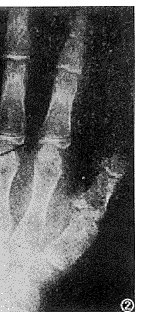

图2 左手正位像。第1、4、5掌骨变短,骨骺早融合,掌骨征阳性;第2指中节和第1、2指末节指骨骨骺已融合